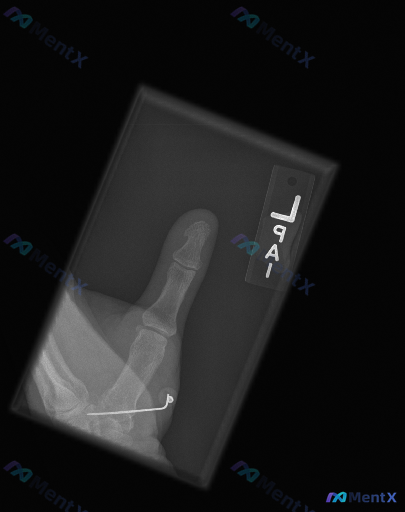

这张左侧拇指X光片,真的只是「正常术后复查」吗?

整理到一张左侧拇指的术后X光片,先放一下基础影像信息:

- 部位:左侧拇指(正位)

- 背景:有近期骨科手术史

- 常规报告印象:第一掌骨基底部可见内固定(克氏针)在位,未见新发骨折征象或内固定失效表现

不过这份深度分析报告里提了几个不一样的视角,甚至说「不是单纯的正常术后复查」。